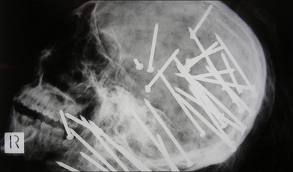

9. A Big Hole in My Head

Perhaps one of the most famous stories of defying the call of death is Phineas Gage. He was a railway worker and was using gunpowder to fill a hole. He added sand, a fuse, and packed the charge down with a big compressing iron. Unluckily for him, the gunpowder blew up while he was doing this and the iron bar powered through his cheek bone and flew out the top of his head – it was later recovered some 25 metres from the site of the incident. A few minutes later legend says he was up and walking. However, the hole in the head removed the part of his brain that controlled social behaviour. He was alive but never quite the same!